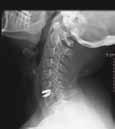

El disco dañado se sustituye por una prótesis móvil, que permite la movilidad del cuello.

Capitaneada por el Dr. Ricardo Arregui, este equipo está compuesto por 3 neu-rocirujanos, 1 traumatólogo y 1 neurólogo, que atienden una media de 5.314 consultas y realizan una media de 307 intervenciones anuales, dando tratamiento integral a cualquier lesión producida en la columna vertebral y el sistema nervioso: traumatismos craneoencefálicos, traumas raquimedulares, hernias de disco...